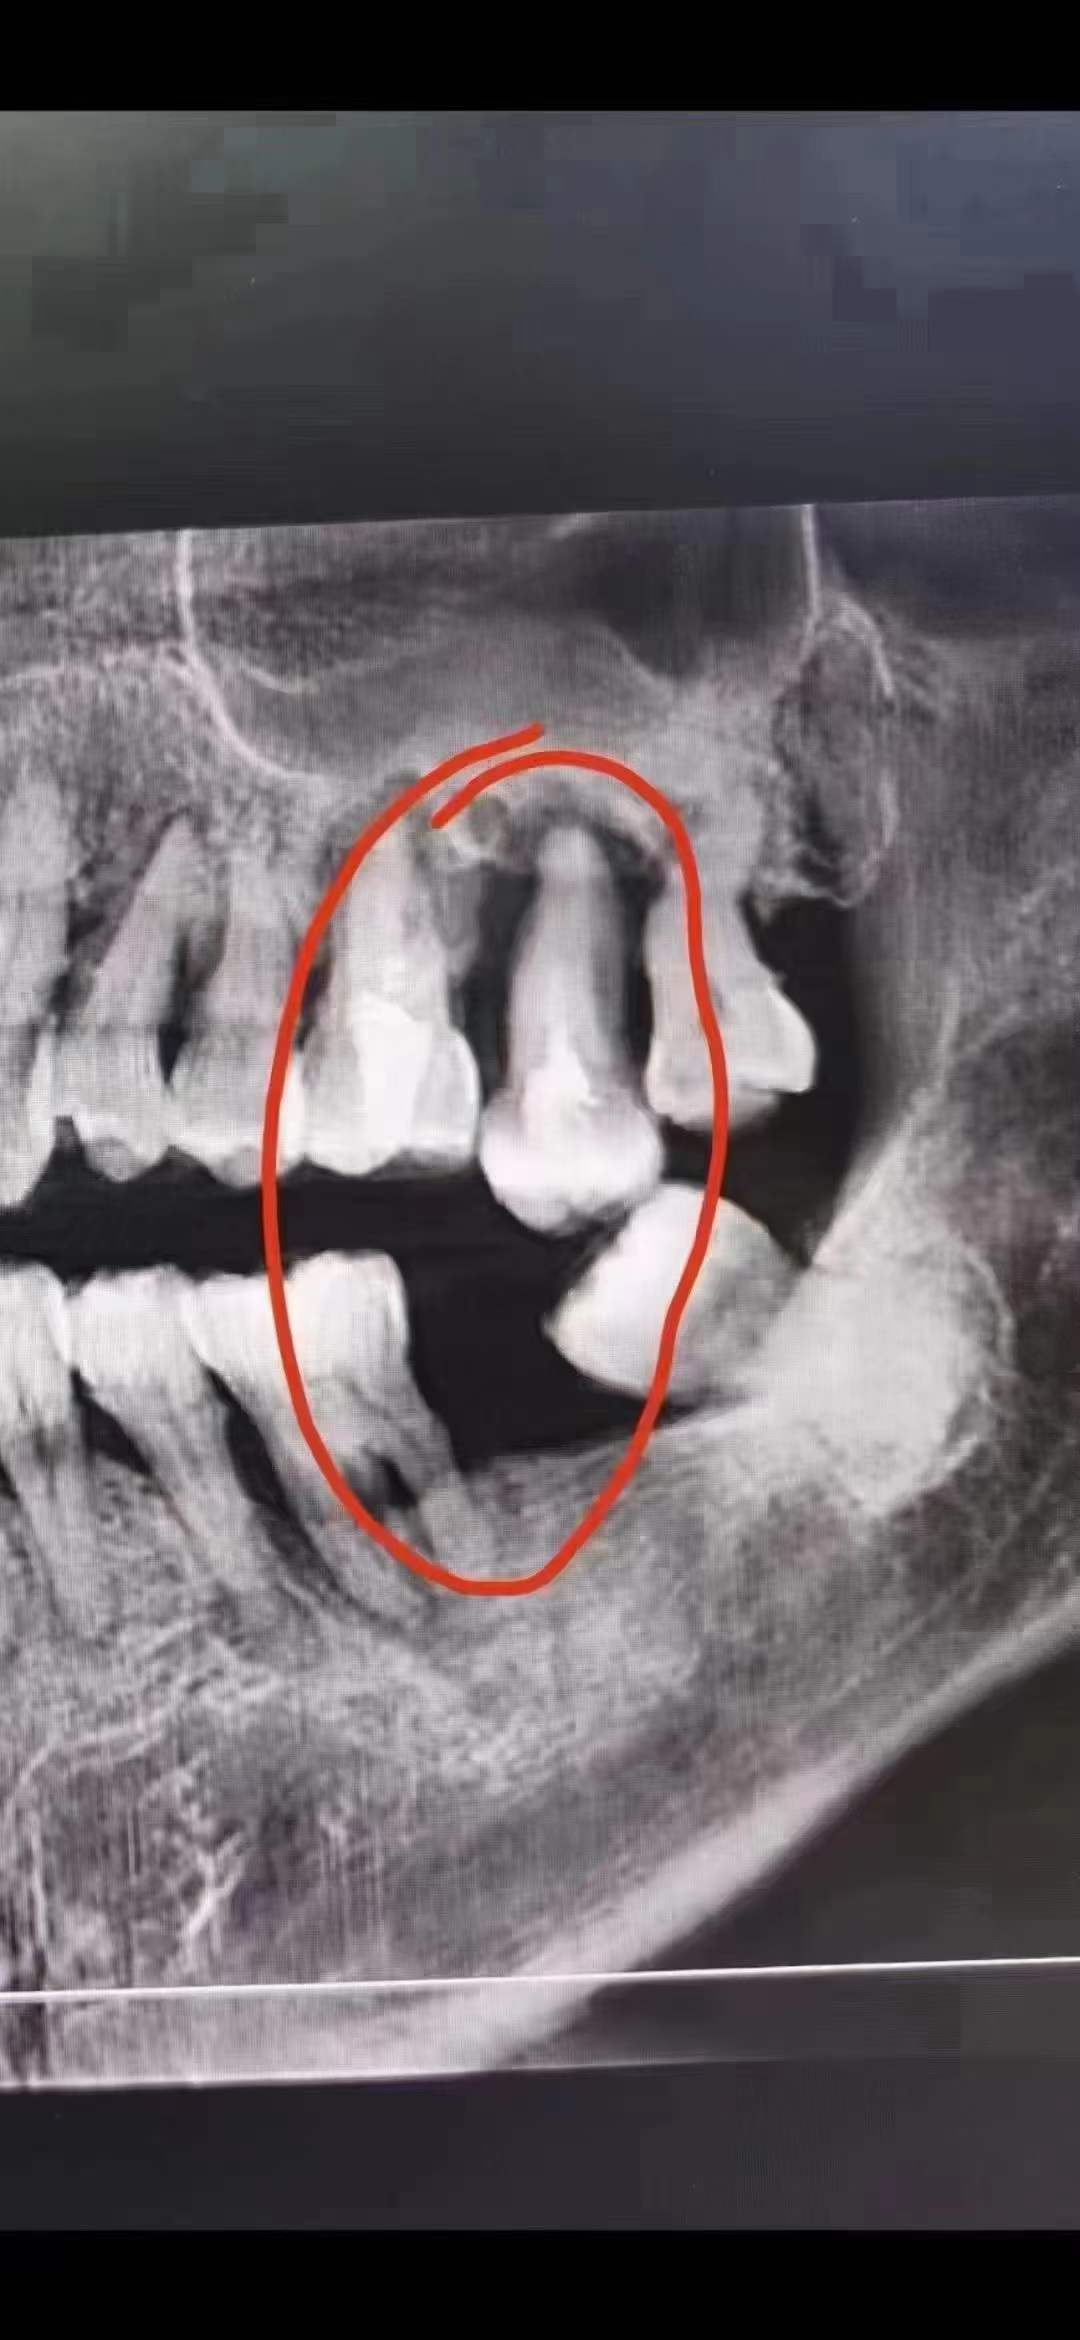

今日分享一例下颌后牙缺失长久不镶牙,导致上颌对颌牙伸长了,虽然种上

对颌牙伸长

对颌牙伸长怎么办呐

缺牙不及时去种牙就会导致对颌牙伸长,垂直间隙过小,给种牙带来难度